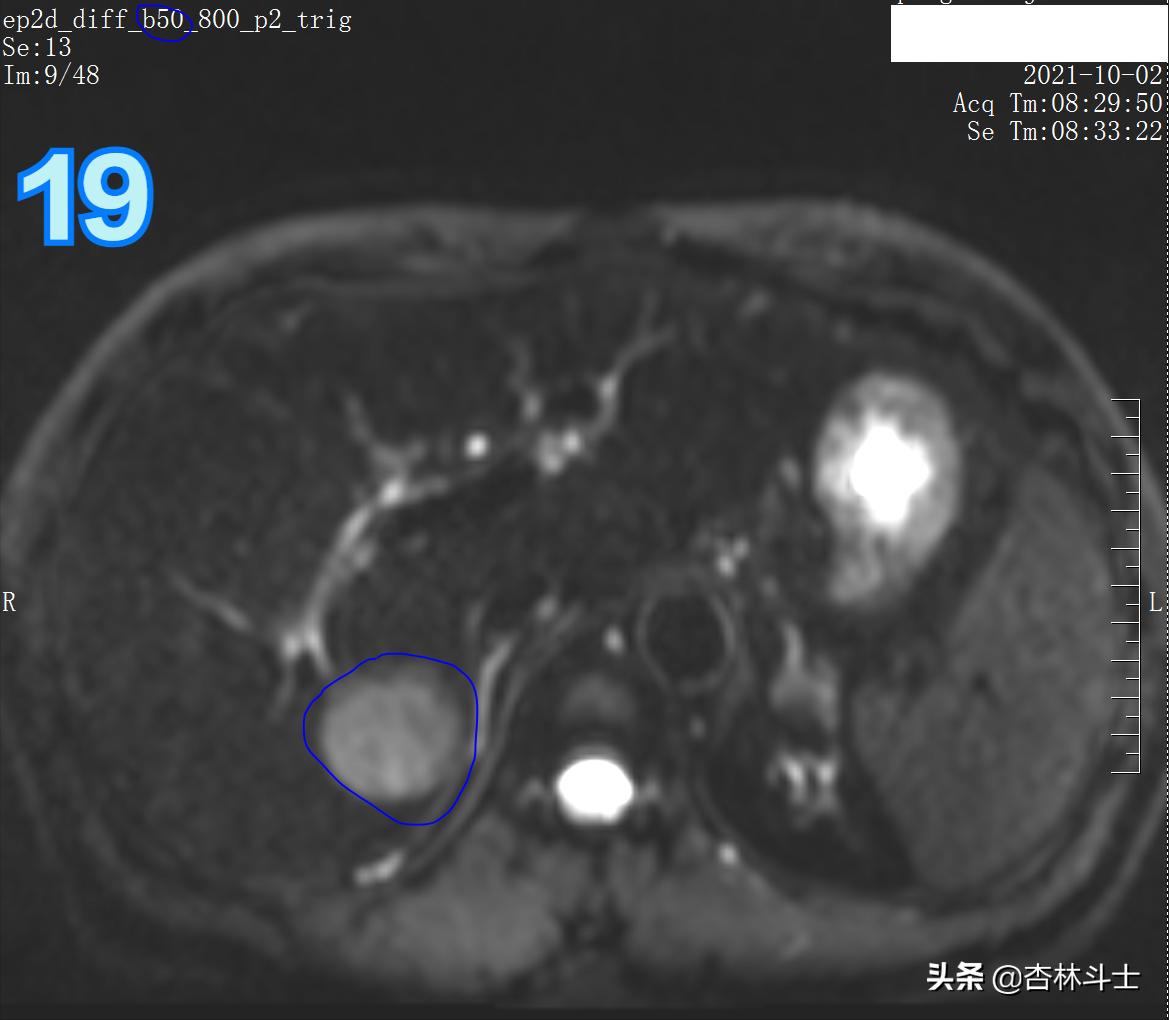

DWI

图19、20 病灶弥散明显受限。